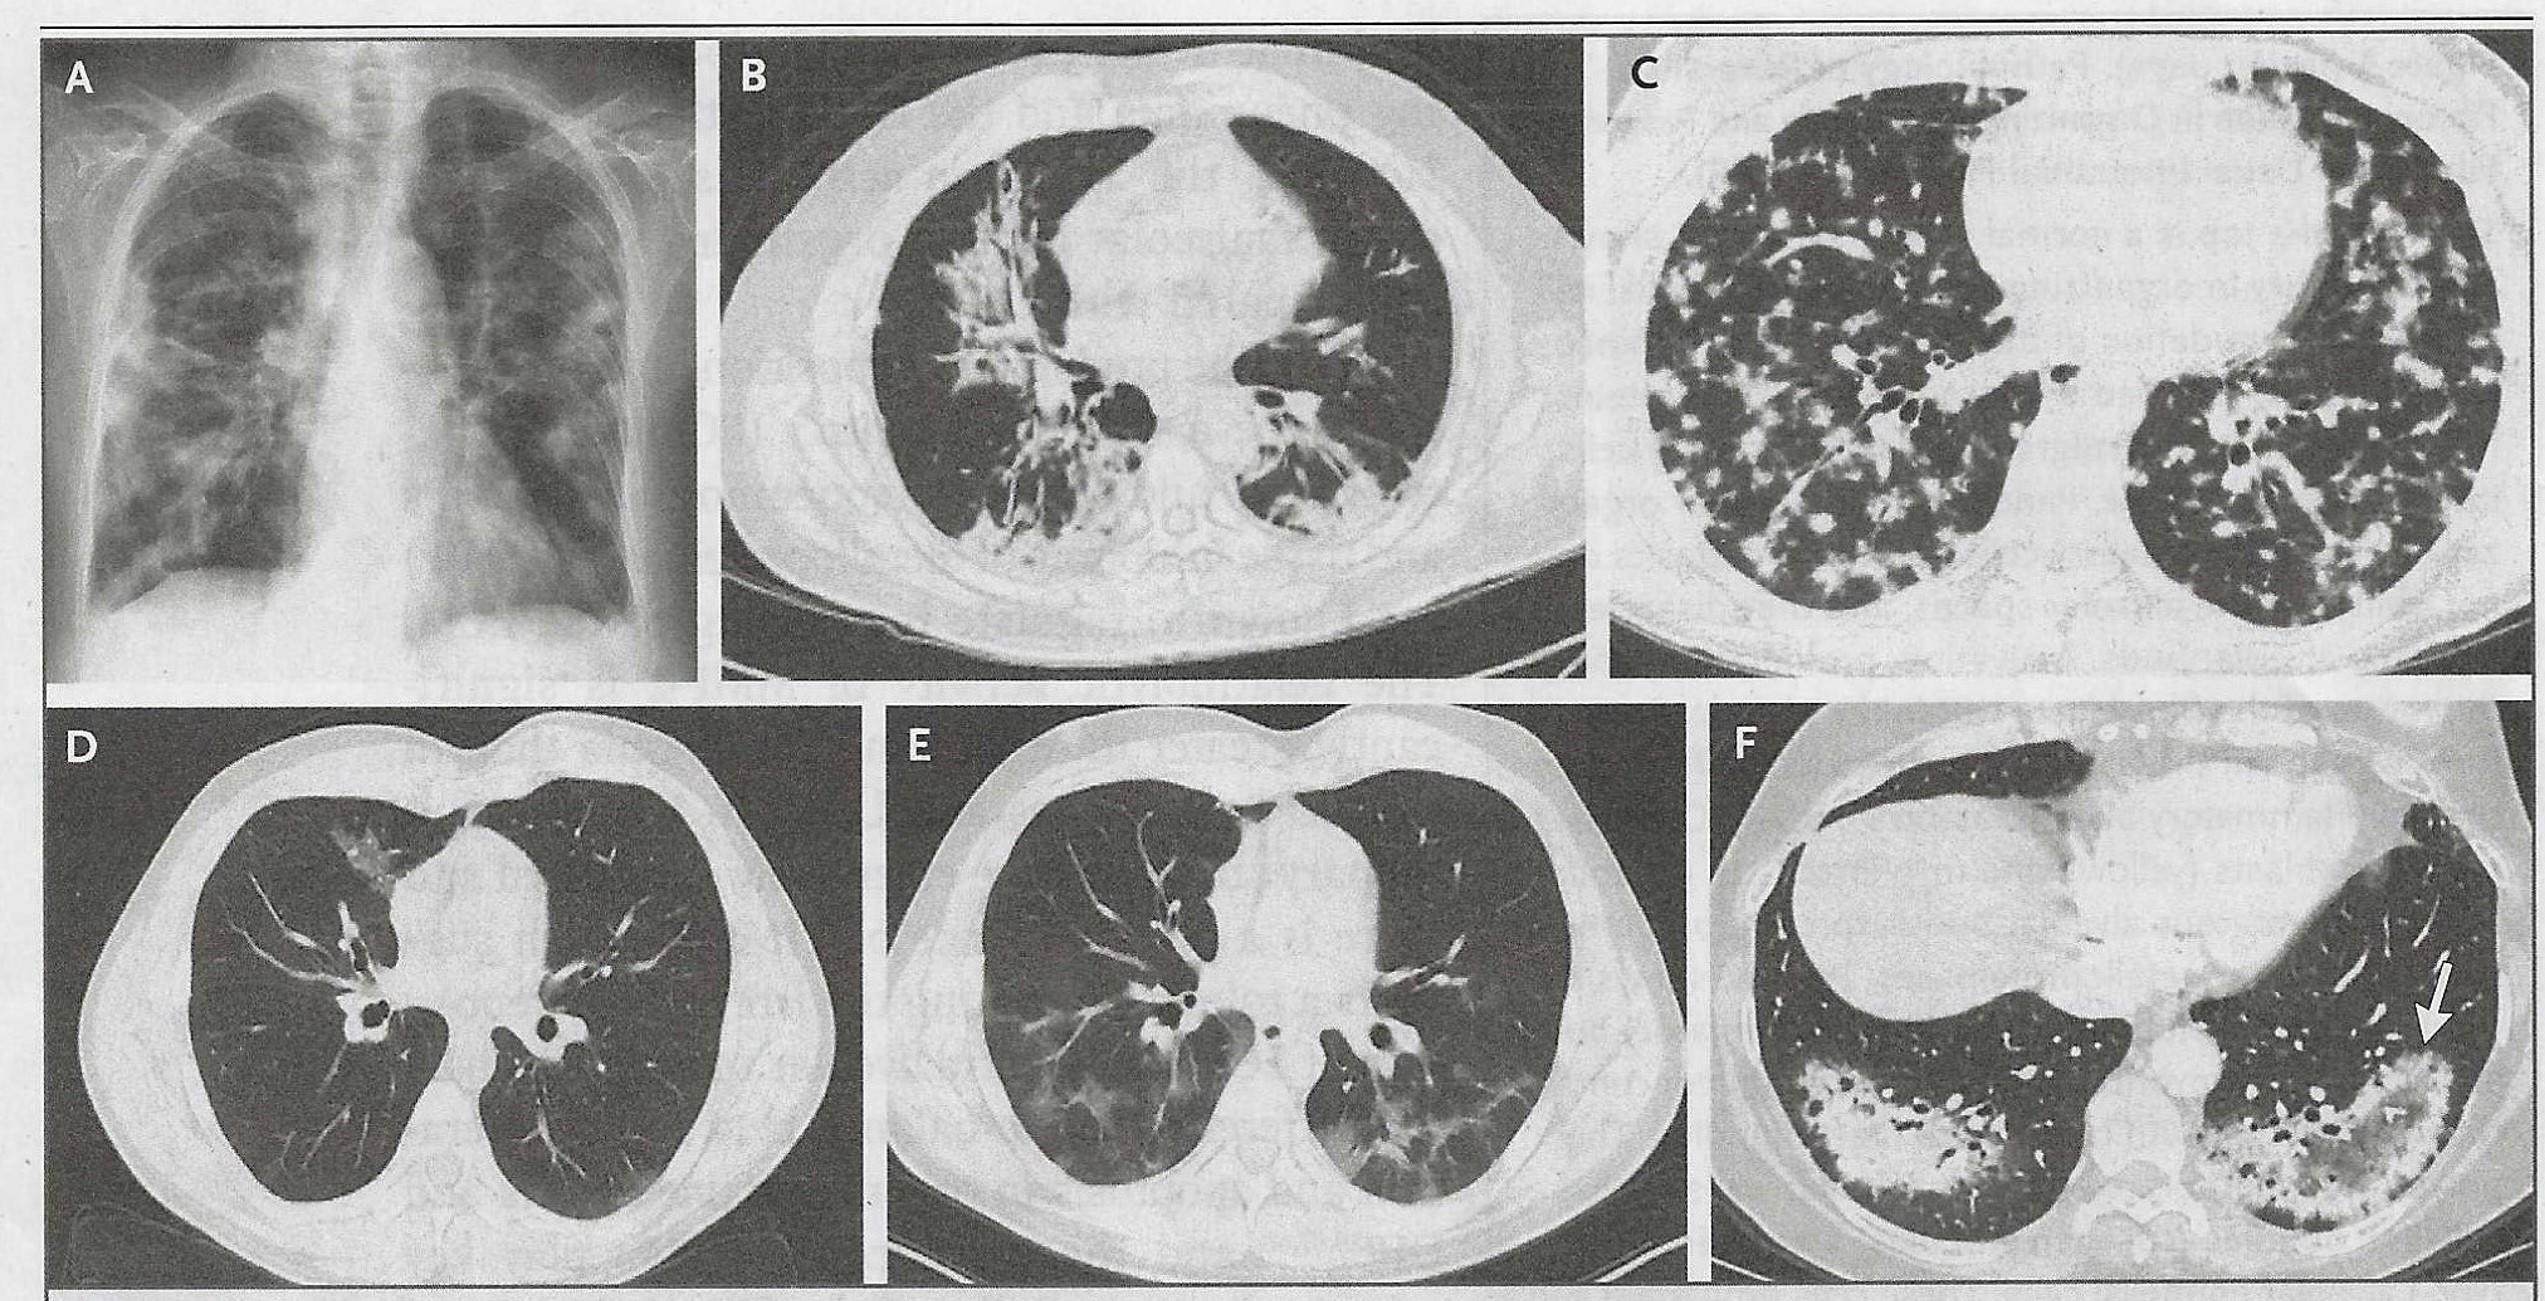

fine inspiratory crackles, egophony, and vocal pectoriloquy. His chest x-ray is shown

below.

On left: patient's chest x-ray showing patchy areas of consolidation and a diffuse increase in interstitial markings (vis-a-vie interstitial fibrosis). These findings were evident during auscultation - diffuse inspiratory crackles (intersitial fibrosis) and egophony and vocal pectoriloquoy (consolidation). This patient had COP-related pulmonary hypertension as indicated by his loud pulmonic closure sound (S2P). On right: chest x-ray and CT scans of other patients with COP.